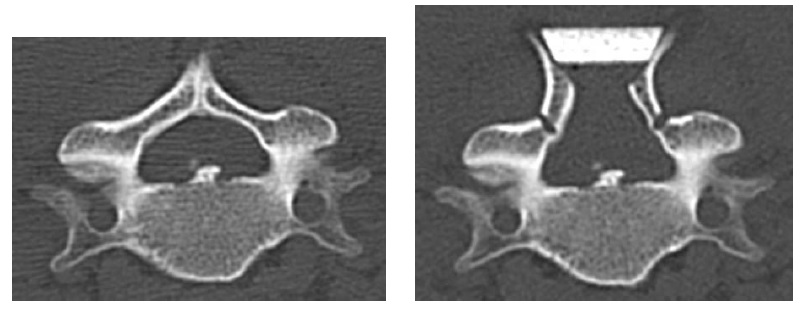

Figure 8: CT at C6 level. Before surgery (left)and after surgery (right) A wide spinal canal was obtained after surgery.